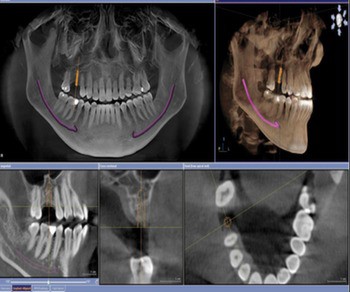

Chụp x quang

Khách hàng sẽ được chụp x-quang bằng máy ConeBeam CT kỹ thuật số 3D.Qua đó, bác sĩ sẽ thấy được tình trạng hô của bạn và đề ra phương pháp phẫu thuật phù hợp để đem lại hiệu quả như ý. Phim hàm Panorex và Cephalometric sẽ xác định chính xác tình trạng hô của hàm, phần xương cần phẫu thuật các thông số kĩ thuật có độ chính xác giúp cho việc phẫu thuật được diễn ra thuận lợi và an toàn.

Phim hàm Panorex và Cephalometric sẽ xác định chính xác tình trạng hô của hàm